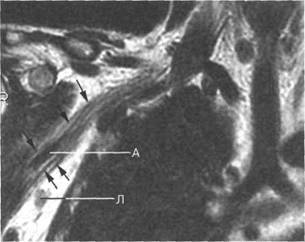

T2-BH(FATSAT).

I располагается позади. Иногда удается хорошо различить ин 10510f510k дивидуальное деление пучков. Ла-